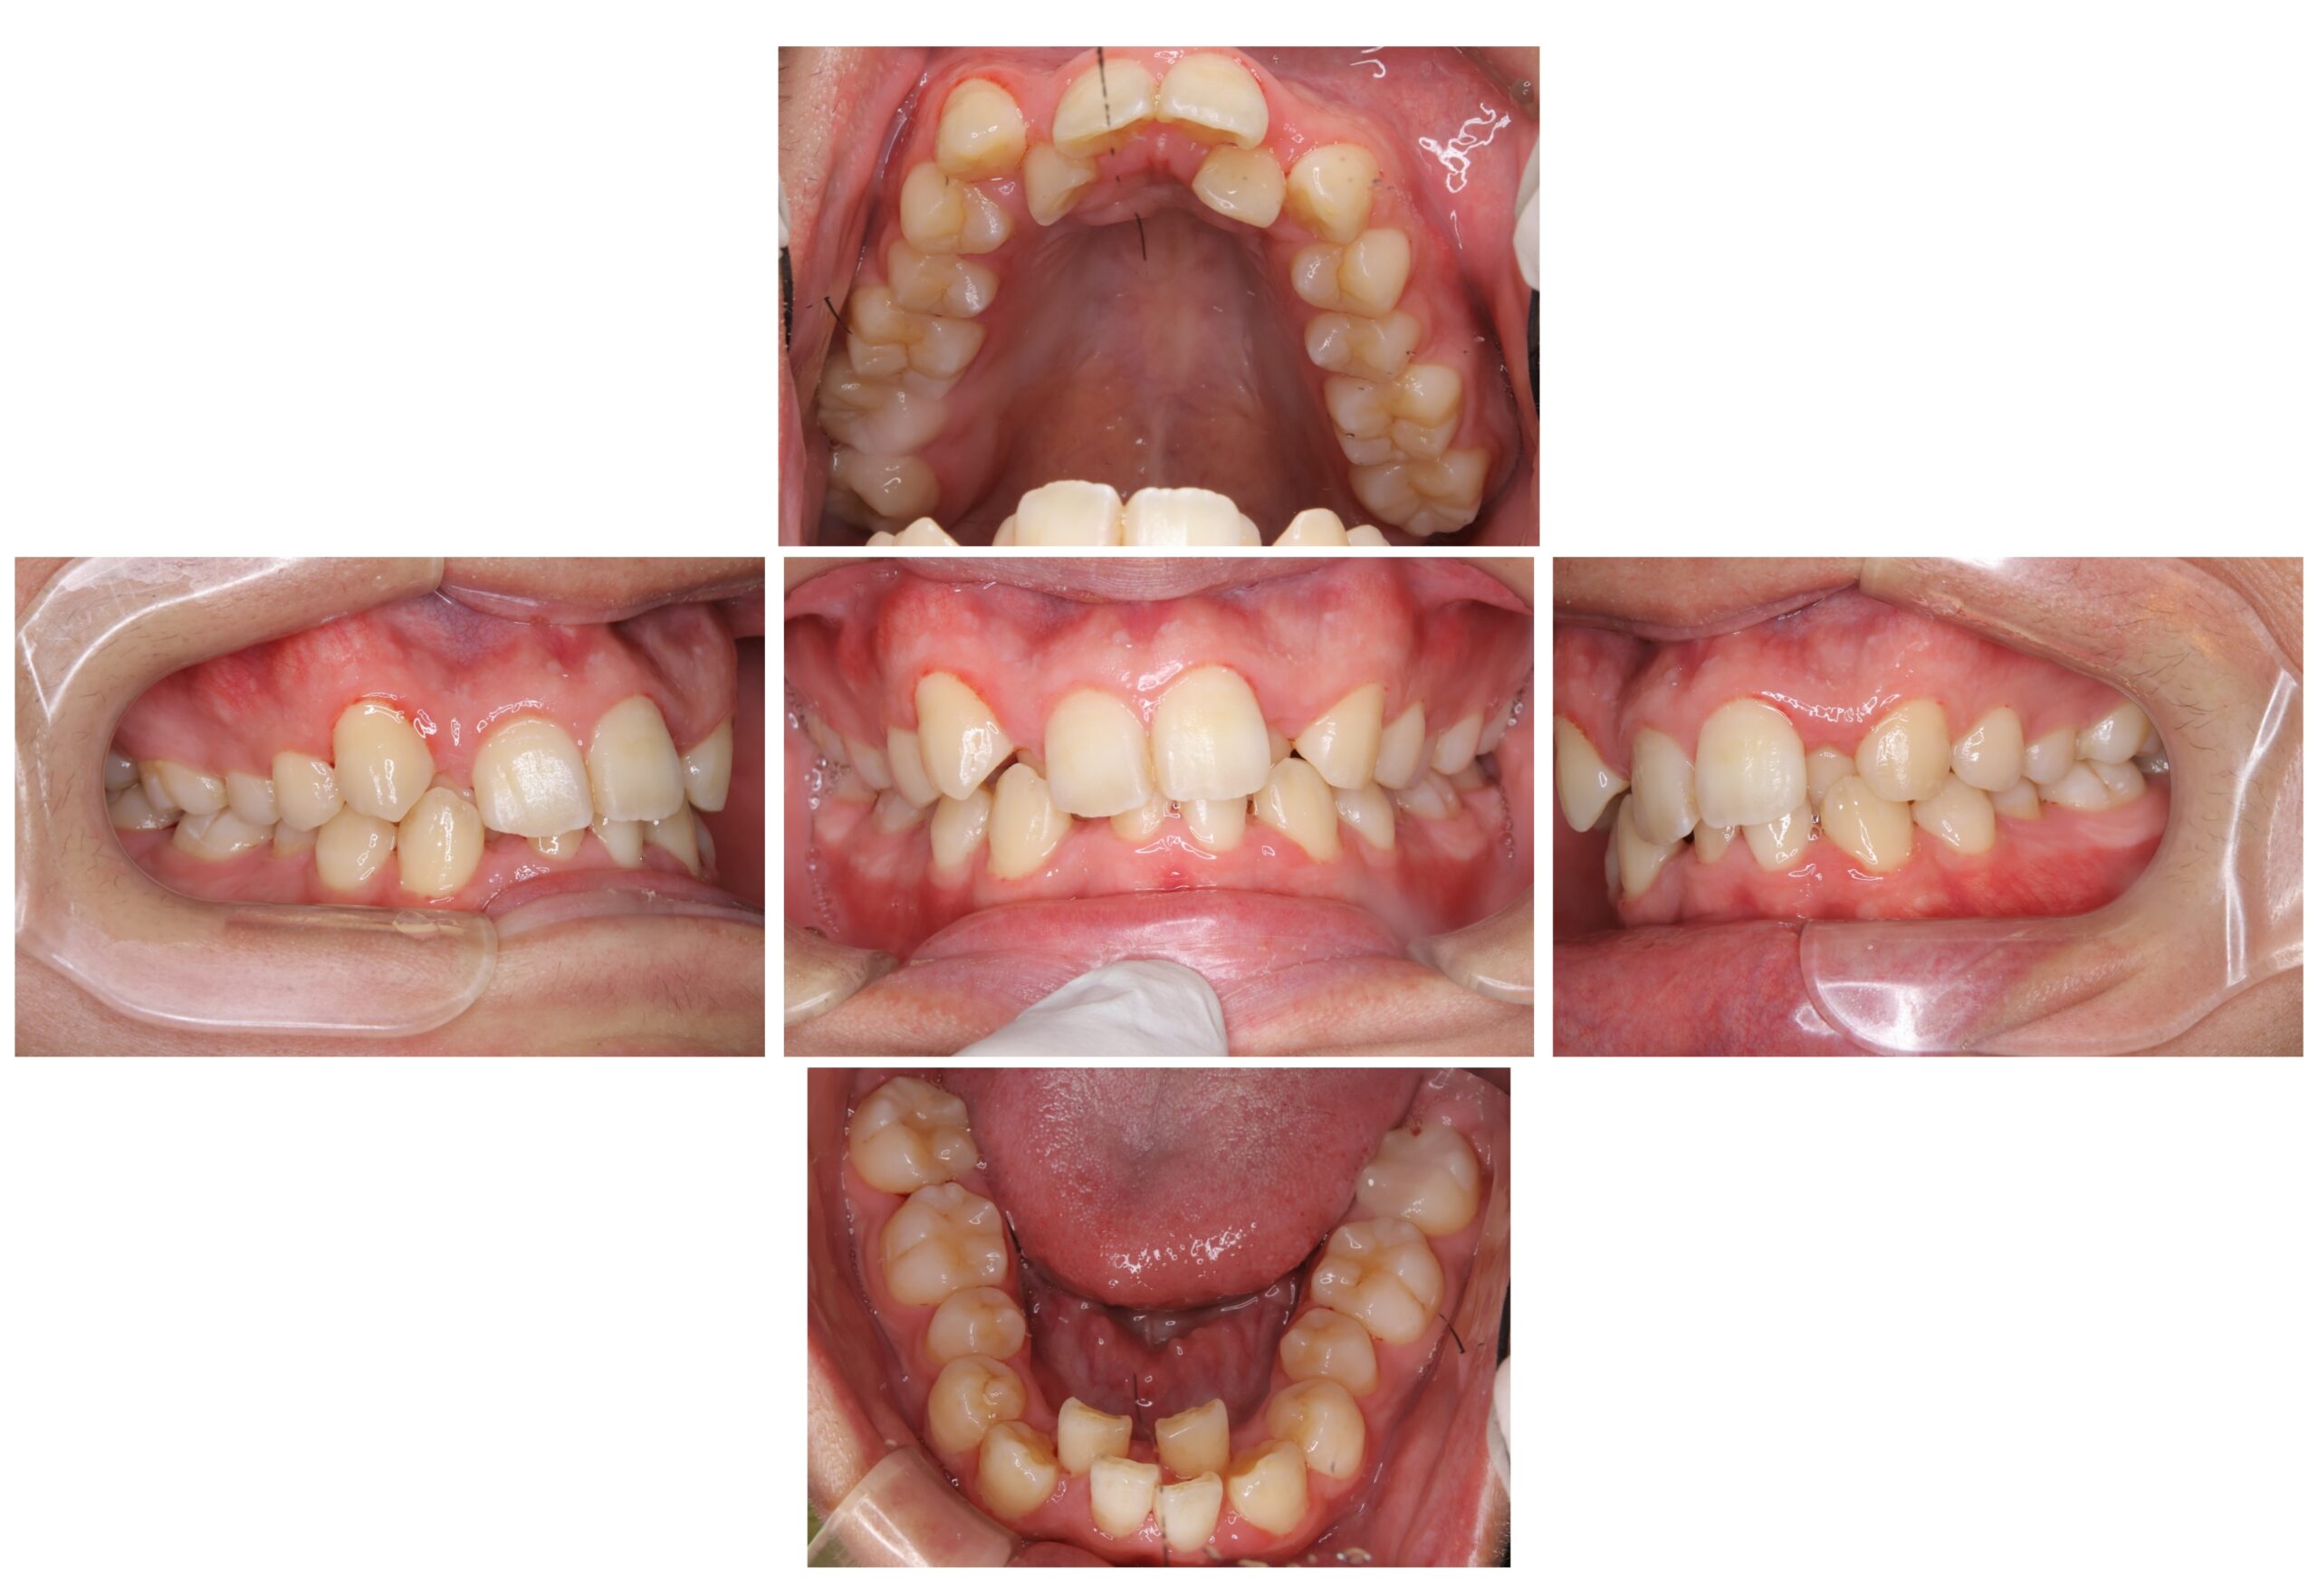

【主訴】

上下前歯の歯並び

【診断名あるいは主な症状】

叢生

【年齢】

30代

【抜⻭部位】

上下顎両側第一小臼歯